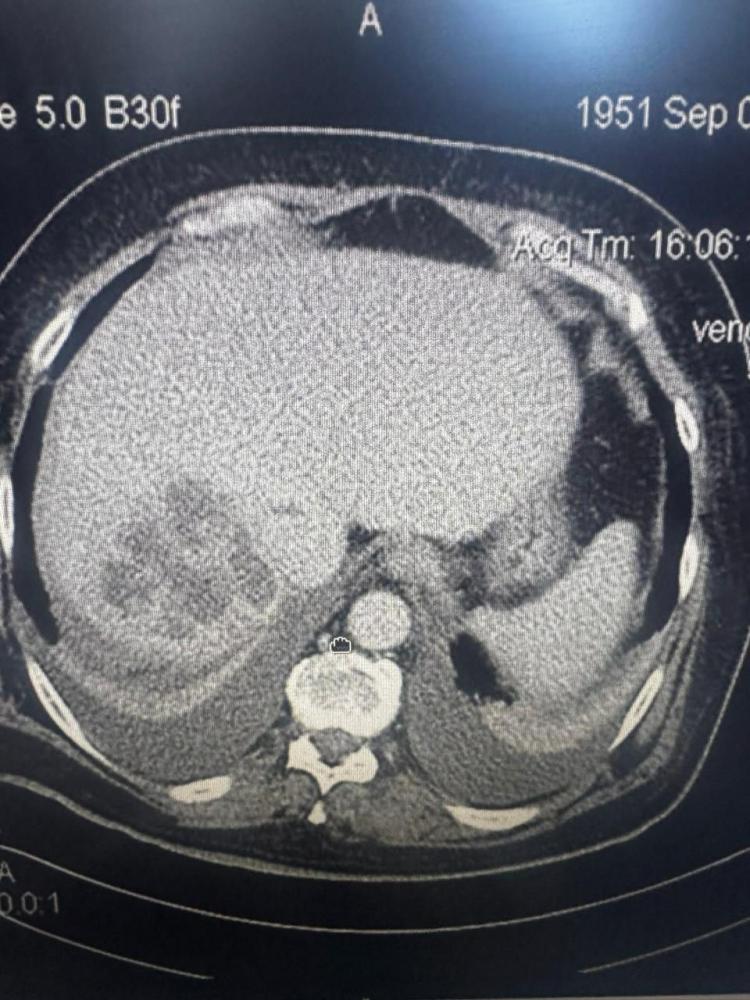

Бригада скорой помощи доставила во Владивостокскую клиническую больницу № 1 53-летнего мужчину, потерявшего сознание от сильных болей в животе. Экстренное УЗИ выявило критическое состояние: огромная киста полностью перекрывала печень и требовала немедленного вмешательства.